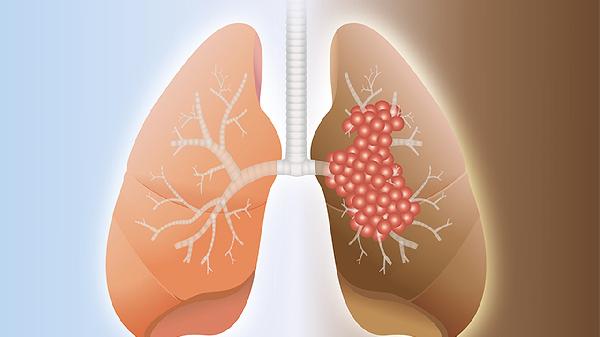

复方万年青胶囊的主要成分为万年青、白花蛇舌草等,具有清热解毒、散结消肿作用。部分临床指南提及该药可能辅助缓解肺癌患者化疗后的毒副反应,如改善乏力、食欲不振等症状。但需注意,其抗肿瘤效果缺乏大规模循证医学证据支持,不能替代手术、放疗或靶向治疗等核心治疗手段。